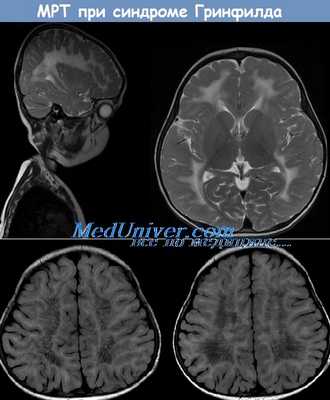

(а) МРТ, Т1-ВИ, сагиттальный срез: определяется снижение интенсивности сигнала от перивентрикулярного и глубокого БВ сливного характера с сохранностью субкортикальных U-волокон. Наблюдаются точечные очаги сохранного перивентрикулярного миелина, хотя они и менее хорошо дифференцируются на сагиттальных срезах.

(б) МРТ, Т2-ВИ, аксиальный срез: визуализируется бабочковидная конфигурация изменений, что характерно для более поздней стадии метахроматической лейкодистрофии (МХЛ). Несмотря на сохранность субкортикальных U-волокон отмечается вовлечение задних бедер внутренних капсул.

(а) МРТ, Т2-ВИ, аксиальный срез: у этого же пациента с поздней стадией МХЛ несмотря на выраженную потерю Объема БВ определяется характерная бабочковидная картина изменений. Наблюдается расширение боковых желудочков (заместительного генеза) и атрофия базальных ганглиев. Кроме того, отмечается повышение интенсивности сигнала от мозолистого тела.

(б) МРТ, Т2-ВИ, аксиальный срез: у этого же пациента определяются повышение интенсивности сигнала сливного характера и выраженная потеря объема БВ. Субкортикальные U-волокна у данного пациента сохранны, однако они часто вовлекаются в процесс на поздней стадии заболевания.